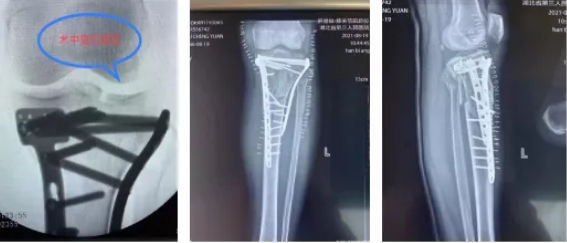

到达医院后,关节创伤骨科值班医生袁文泽和主治医师刘超迅速接诊,在查看伤情后随即安排检查,X光结果提示:左膝胫骨平台内外后三个方向塌陷骨折,需要手术治疗。经过一个星期的跟骨牵引、消肿、止痛抗凝等治疗,吴师傅伤情稳定,10月18日,关节创伤骨科主任王显勋根据伤者具体情况,选择为其进行内外后三个方向钢板固定术,通过胫骨平台内外侧两块钢板巧妙恢复胫骨平台关节面的平整,同时将骨折固定牢靠,两个小时后吴师傅被顺利推出手术室。

(术中、术后X光片)

在医护人员贴心的服务和耐心的指导下,吴师傅积极配合治疗,术后两周膝关节就能正常屈伸活动,预计一个月后就能扶拐杖自行行走。